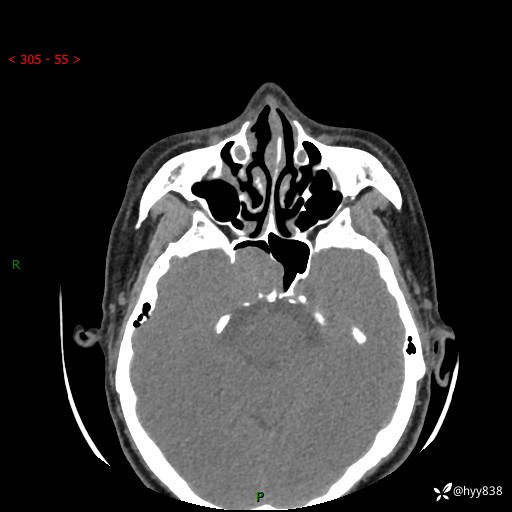

蝶鞍CT平扫